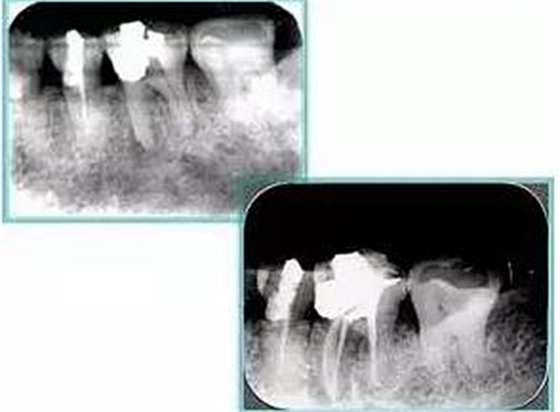

左圖和上圖為干髓治療后牙齒,齲齒疏通后進(jìn)行根管充填。

如圖為塑化加根充處理后牙齒 X 線(xiàn)片。